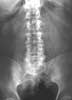

The next steps. The ECG showed sinus rhythm and no signs of myocardial ischemia. Because the differential diagnosis includes nephrolithiasis, many authorities recommend obtaining a screening radiograph of the kidneys, ureter, and bladder (KUB) to look for stones in this setting. This patient's KUB is shown in Figure 3.

An abdominal series should consist of 3 views, including flat, upright, and upright chest films. These radiographs are helpful only for diagnosing obstruction, perforation, foreign body, and occasionally, volvulus.27 Plain radiography is not a good screening tool for nephrolithiasis because the sensitivity is only 45% to 58%.28 Furthermore, clinicians must carefully interpret films that will have a delayed reading by a radiologist.

This patient had an AAA, which can have a subtle appearance on an abdominal x-ray film. In patients with AAA, abdominal radiographs may show a calcified outline of the aorta and lateral displacement of the calcified wall, which suggests the presence of the aneurysm. A sign of leakage or rupture of an AAA is the obliteration of the ipsilateral iliopsoas margin. In a patient with appropriate symptoms, the sensitivity of abdominal radiography for AAA is only 60% to 70%. Therefore, plain films should not be the initial diagnostic study when AAA is suspected. Instead, ultrasonography or CT should be used (Table 2).